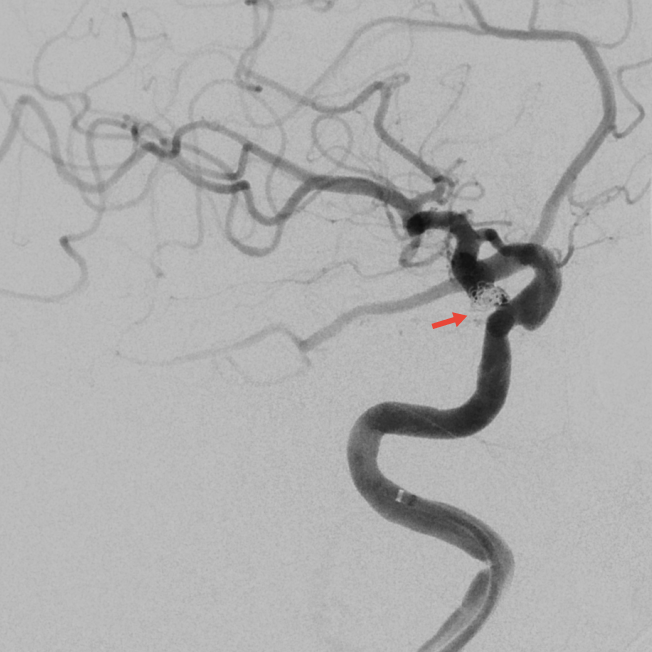

手术当日,在导管室、麻醉科的协作下,神经外科副主任医师刘磊带领介入团队在全麻下为患者实施脑动脉造影+右侧后交通动脉瘤弹簧圈栓塞术。造影显示患者为双侧颈内动脉多发动脉瘤,结合出血位置与动脉瘤形态,团队精准判断右侧后交通动脉瘤为破裂责任病灶。该动脉瘤形态不规则,且瘤颈发出胚胎型大脑后动脉,手术需在完全栓塞动脉瘤的同时确保分支血管通畅。团队克服动脉迂曲与硬化等困难,经过两小时精细操作,成功实现动脉瘤近致密栓塞,载瘤动脉及分支血流通畅。

▲术后即刻造影见动脉瘤近致密栓塞,载瘤动脉及胚胎型大脑后动脉通畅